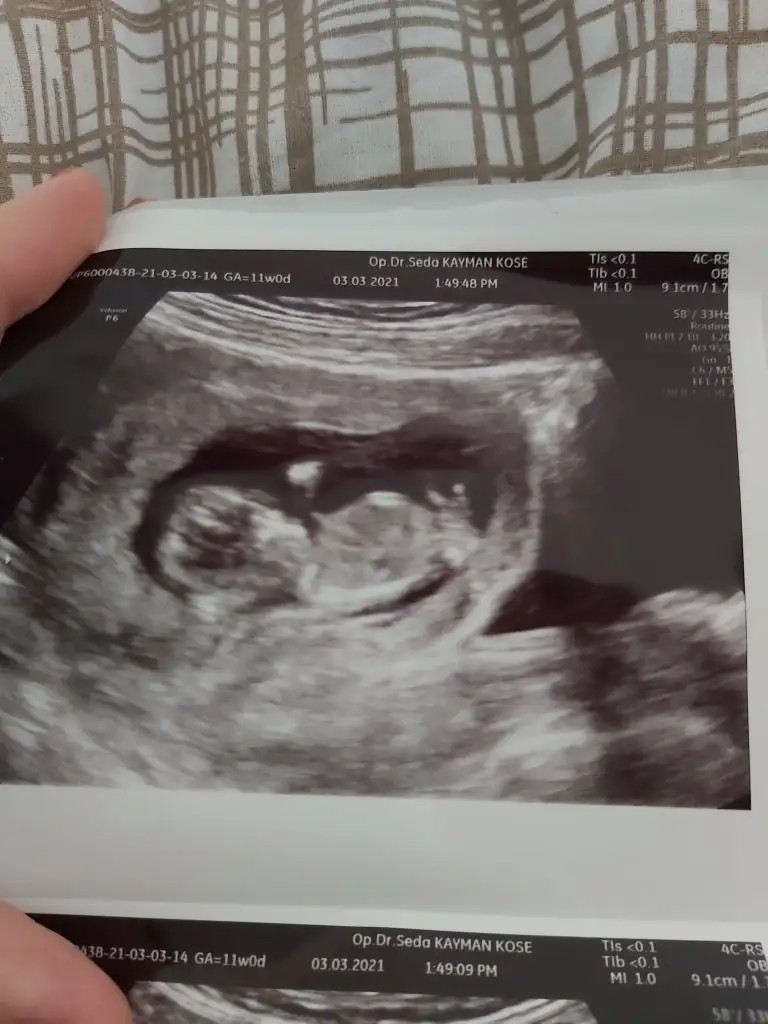

11. Haftamız yakında bitecek benımki böyle poz verdi sence ?

Şimdilik kız yönünde tabiki en iyi 12-13 hafta olursa paylasin11. Haftamız yakında bitecek benımki böyle poz verdi sence ?

Ayy herkes erkek diyor cok sevindim insallah kızdırŞimdilik kız yönünde tabiki en iyi 12-13 hafta olursa paylasinemin olamadım